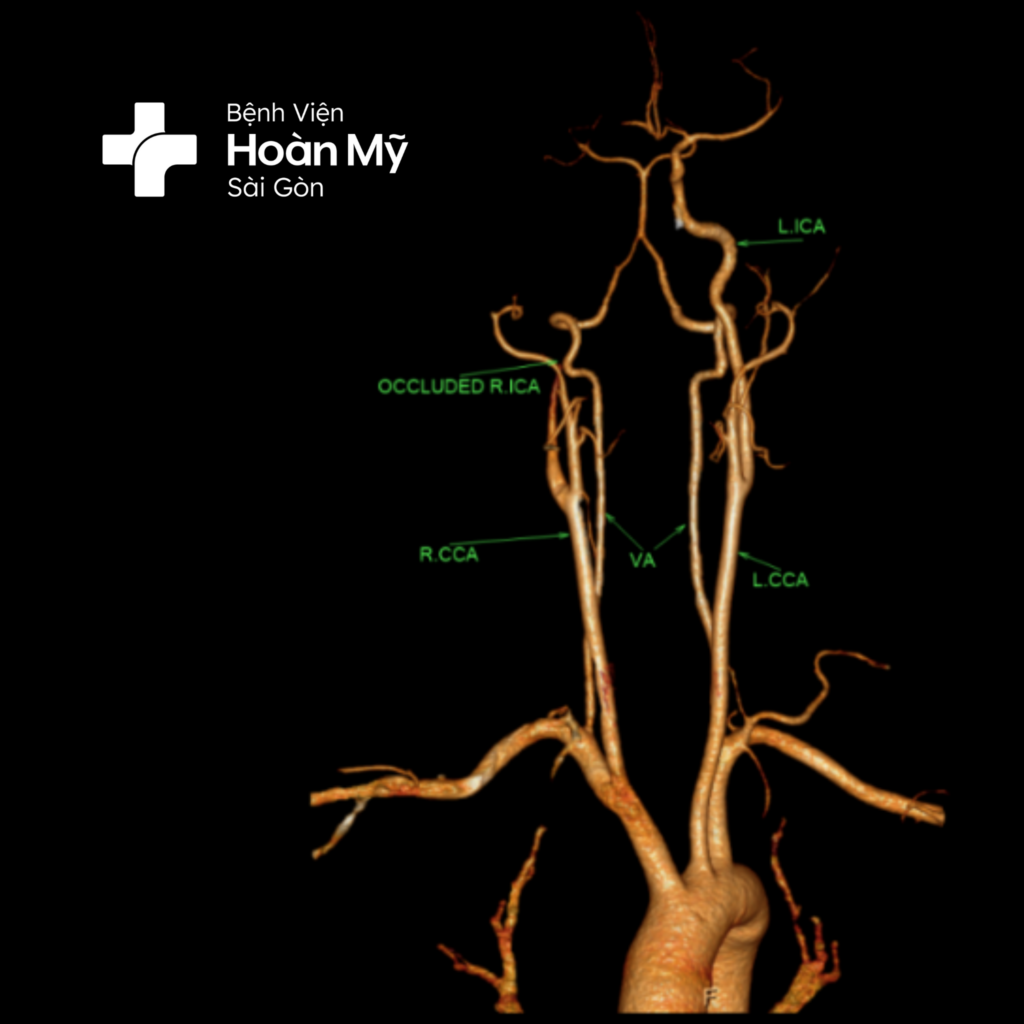

Ngay khi người bệnh vào viện, nhận thấy tình trạng liệt hoàn toàn 1/2 người trái, nói khó khăn, liệt mặt trung ương trái. Qua thăm khám, chúng tôi chẩn đoán anh H. bị đột quỵ, ngay lập tức khởi động quy trình Code Stroke - báo động cấp cứu đột quỵ, hội chẩn cùng bác sĩ chuyên khoa và cho người bệnh chụp CT não khẩn. Kết quả chụp CT não cho thấy người bệnh bị nhồi máu não cấp giờ thứ I do tắc hoàn toàn động mạch cảnh trong phải và động mạch não giữa phải” - BS. Thiên cho biết

Hình ảnh CT mạch máu não trước can thiệp: Tắc hoàn toàn ĐM cảnh trong và não giữa phải